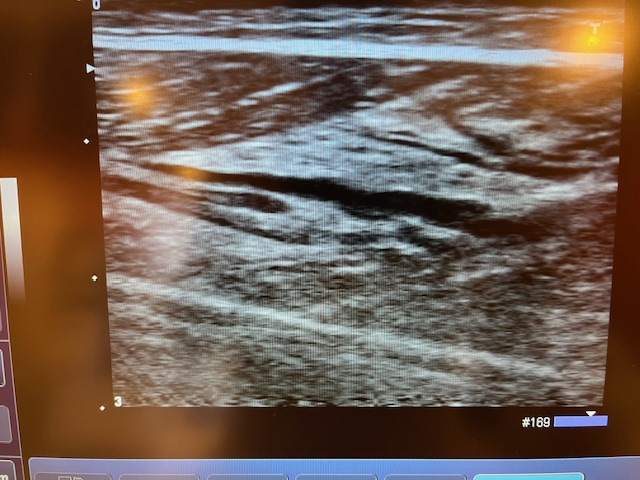

エコーを撮ってみると、

このように筋肉が裂けているような感じになっています。

完全にふくらはぎの肉離れ。。